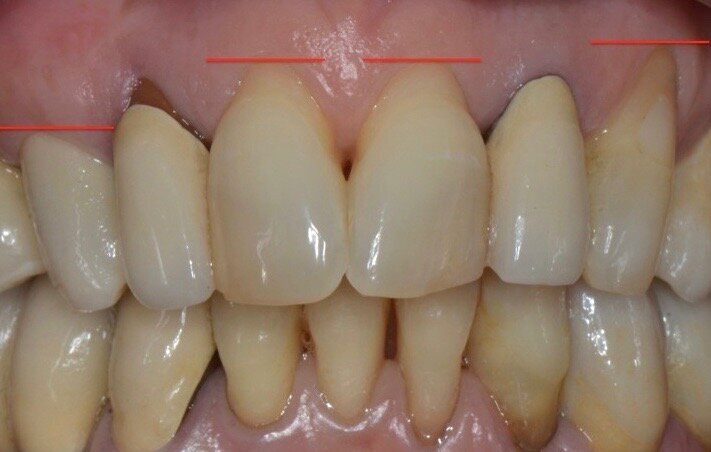

Riguardo al comparto intraorale, dalle radiografie diagnostiche e dall’esame parodontale e occlusale sono emersi aspetti che meritavano una correzione anche nei settori posteriori, ma la paziente ha deciso di effettuare inizialmente il trattamento dei soli gruppi frontali superiore e inferiore demandando a un momento successivo le problematiche dei quadranti posteriori (Figg. 2-6). Nel gruppo frontale superiore si possono notare recessioni gengivali sugli incisivi centrali, che sono anche molto ruotati, e sul canino di sinistra; corone in metallo-ceramica sugli incisivi laterali con esposizione del bordino metallico e una corona in ceramica metal-free sul canino di destra. Inoltre è molto evidente lo squilibrio delle parabole gengivali tra i due canini, per cui per ristabilire un’estetica ottimale sarà necessario anche interessare i tessuti molli eseguendo una chirurgia resettiva sul canino di destra e, al contrario, un lembo a posizionamento coronale sul canino di sinistra (Fig. 7).

Inizialmente vengono applicati i provvisori prelimatura (Fig. 9) utilizzati anche come mock-up per passare dopo le opportune valutazioni estetiche (Figg. 10, 11) a una seconda serie di provvisori che ci accompagnaranno durante la fase chirurgica e il tempo di guarigione e maturazione dei tessuti. Prima si procede con la chirurgia resettiva (ORS) sul canino superiore destro per alzare la parabola gengivale a livello degli altri denti frontali; questo intervento viene eseguito con un approccio “delicato” e meno invasivo possibile per non penalizzare l’estetica della corona preesistente sul primo premolare superiore destro.

Dopo circa un mese viene eseguito un lembo a scorrimento coronale con innesto di tessuto connettivo (CAF+CTG) prelevato dal palato con la “Tecnica di Langer e Langer mod. J.Bruno” per coprire la recessione sul canino superiore sinistro e ispessire il tessuto sopra il quale verrà posizionata una faccetta in ceramica (Figg. 12-17). A due mesi dal CAF+CTG si può notare la maturazione dell’innesto con un ottimale spessore mantenuto e lo spazio guadagnato sul canino controlaterale con la ORS (Figg. 18, 19).